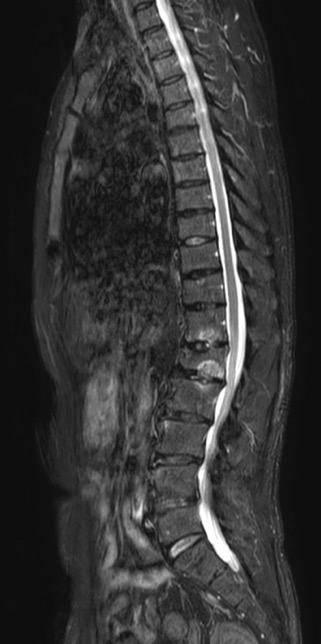

MRI spine: multiple compression fracture from T5 to L2

• MRI (Spine): Vertebral compression fractures at L1–L3, multiple lytic lesions in vertebral bodies, lumbar disc herniation.